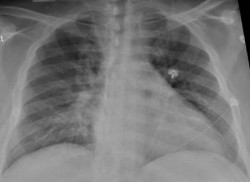

Un nuevo atlas celular de los pulmones revela por qué el virus es mortal y diferente

Un nuevo estudio del Colegio de Médicos y Cirujanos Vagelos de la Universidad de Columbia y del Centro Oncológico Integral Herbert Irving (Estados Unidos) ha dibujado la imagen más detallada hasta ahora de la infección por SARS-CoV-2 en el pulmón, revelando los mecanismos que dan lugar a la COVID-19 letal, y puede explicar las complicaciones a largo plazo y mostrar cómo la COVID-19 difiere de otras enfermedades infecciosas.